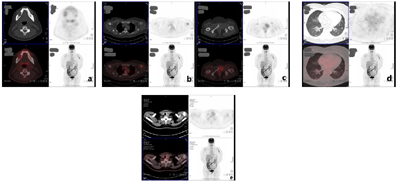

患者女性,50岁,于2020年4月无明显诱因出现左上臂肿痛,活动受限等症状,自行休息后未见明显缓解,遂就诊于当地医院,行X光片提示:左肱骨上段骨质破坏(图1)。后于2020年4月30日行PET/CT全身显像(图2)提示:甲状腺左侧叶混杂密度结节,代谢稍活跃;双肺多发结节,代谢活性未见明显增高;下颌骨右侧支、左侧肱骨上段、左侧耻骨及第4腰椎棘突骨质破坏,代谢活跃。为进一步明确诊断,患者于2020年5月14日在外院行"左肱骨中上段肿瘤广泛切除,人工肱骨头置换术",术后病理提示:符合甲状腺滤泡性癌转移。遂于2020年6月1日再次于该院行"双侧甲状腺全部切除术+颈部淋巴结清扫术(Ⅲ、Ⅳ及Ⅶ区)+喉返神经探查术",术后病理(图3)提示:1、(左侧甲状腺)广泛浸润性甲状腺滤泡癌,肿瘤大小5.0 cm×4.0 cm×2.0 cm,血管浸润>4个血管,未见明确神经侵犯;2、(右侧甲状腺)甲状腺滤泡性肿瘤,考虑为滤泡癌累及。为进一步治疗,患者于2020年7月28日、2021年1月13日入住我院行131I治疗。

入院后完善相关检查后,根据2015版美国甲状腺协会(ATA)分化型甲状腺癌诊治指南、2018版美国癌症联合委员会(AJCC)和国际抗癌联盟(UICC)联合制定的第8版甲状腺癌TNM分期进行病情评估,患者肿瘤复发危险分层为高危,TNM分期为T3aN0M1,Ⅱ期。分别于2020年7月30日(250 mCi)、2021年1月15日(250 mCi)予以131I治疗,治疗后第3天行全身碘扫描及断层融合显像(图4,图5)。

Li等[9]对1608例出现远处转移的甲状腺癌患者的研究数据表示对于中高分化的甲状腺癌患者,131I可以精准治疗转移病灶。Aubrey等[10]通过对一例FTC伴广泛脊柱转移的病例随访发现131I治疗的疗效具有一定的持久性,认为在经过131I治疗后且Tg呈进行性下降的过程中,患者暂时不需要立即做其他治疗。本例患者经过2次131I治疗后,通过观察及随访患者的Tg指标及影像学指标,提示患者病情较前改善。证明131I治疗对DTC伴肺、骨转移患者治疗的有效性,尤其对于那些摄碘效果良好的病灶的疗效更为显著。然而通过比较PET/CT及碘显像发现,本例患者的远处转移灶中,双肺转移瘤的18F-FDG阴性但131I阳性,而骨转移灶则呈现18F-FDG和131I均为阳性。通常来说,摄取18F-FDG的甲状腺肿瘤分化程度较低且侵袭性较高,而摄取131I则提示甲状腺肿瘤保留分化的特点[11],王丹阳等[12]研究认为18F-FDG和131I同时摄取的现象可能是由131I摄取阳性细胞失分化,使不同分化程度的肿瘤细胞共存于同一病灶内所致。18F-FDG和131I摄取的双阳性可能提示病灶具有失分化的倾向。因此该患者后续也有进展为碘难治性甲状腺癌的风险。